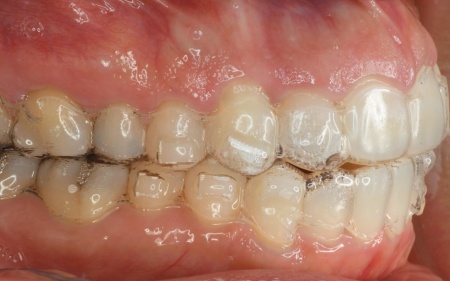

拝見したところ、奥歯で噛んだ際に上下の前歯が触れ合わず、隙間ができている状態でした。

これは開咬(かいこう)と呼ばれ、前歯で食べ物を噛み切るのが難しい噛み合わせです。

加えて全体的に歯が重なり合ってデコボコに生えており、歯磨きがしにくく、審美性にも悪影響がでています。